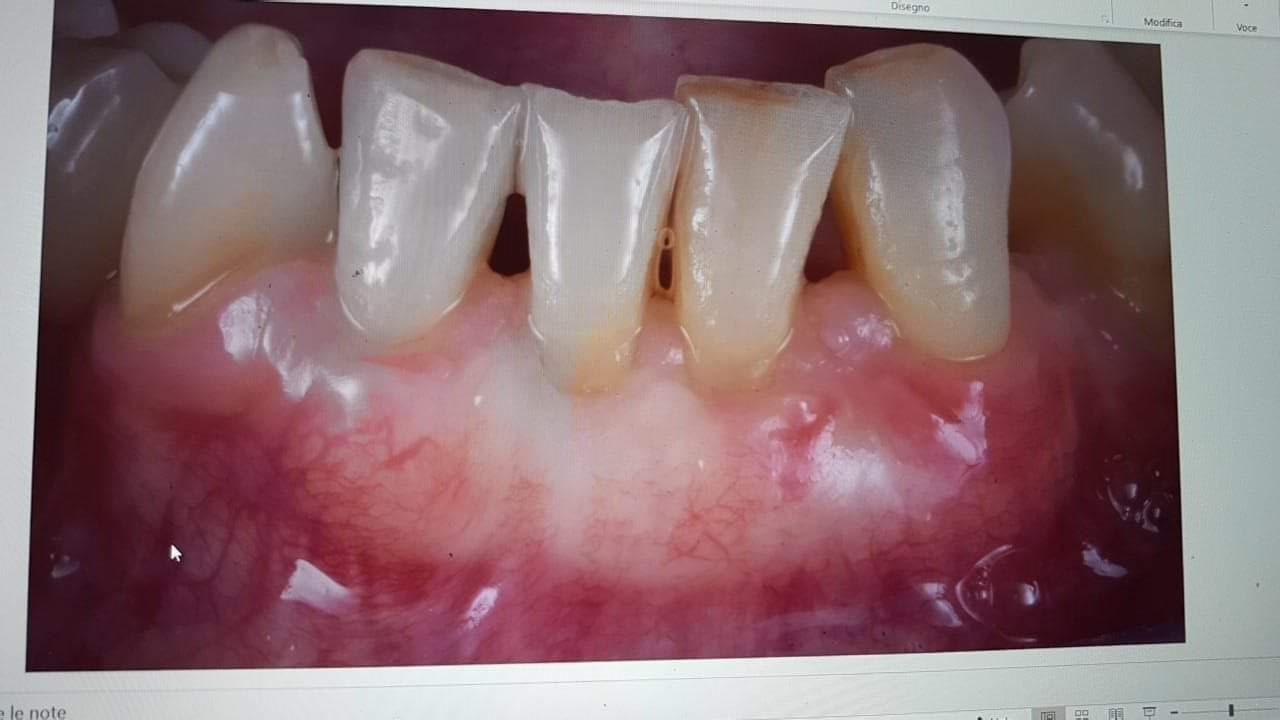

Il caso era questo.

WhatsApp Image 2019-03-13 at 18.15.02